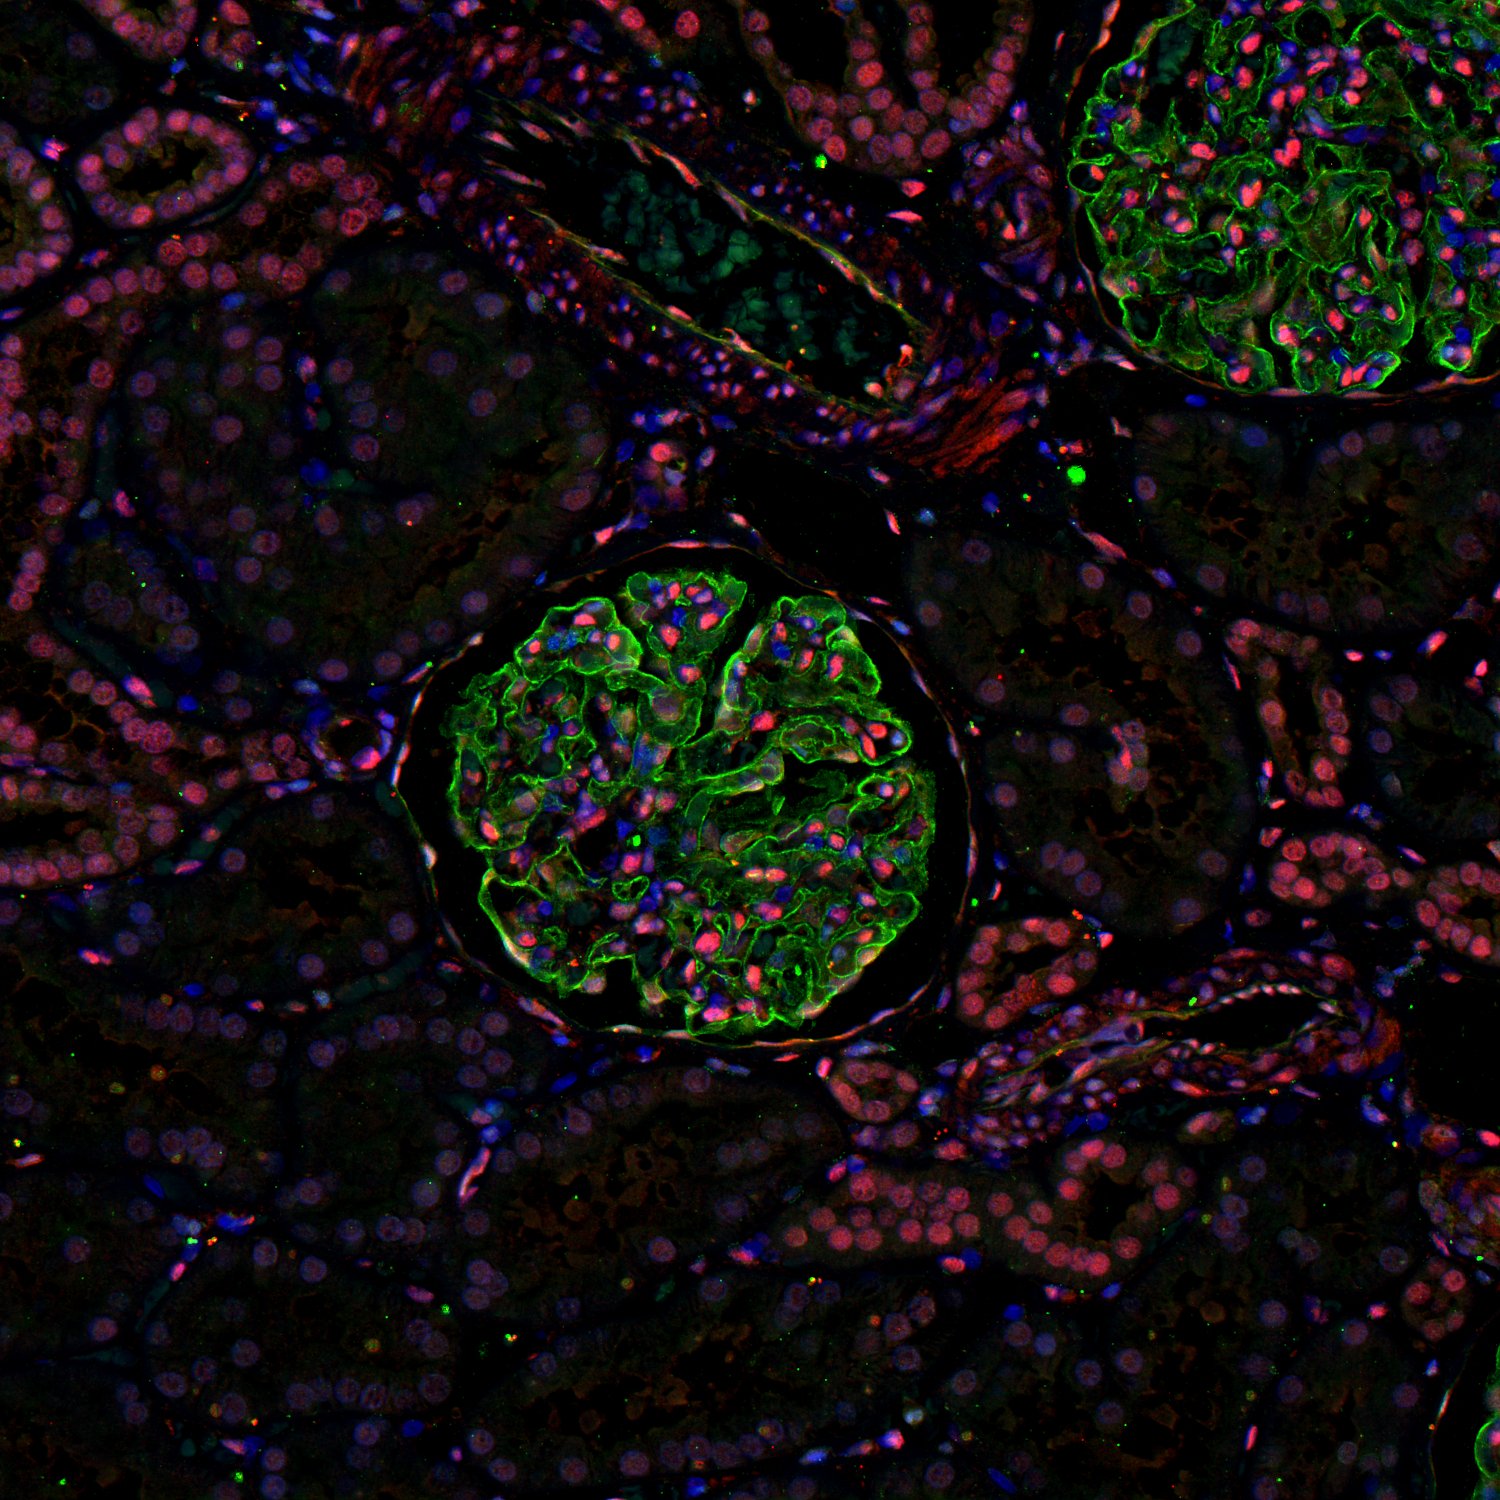

Staining of human kidney with rabbit anti-MEF2A (red) and Synaptopodin (green)